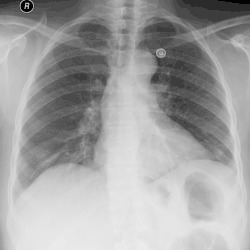

Tension pneumothorax

Tension pneumothorax is an emergent condition in which air gets trapped in the space between the chest wall and the lung. This space is referred to as the pleural space. Because air can't escape from this space, the air pocket grows larger and larger, resulting in the lung collapse closest to the pneumothorax. Forces are transmitted to the mediastinum and effectively "push" the mediastinal structures to the opposite side of the chest.[5]